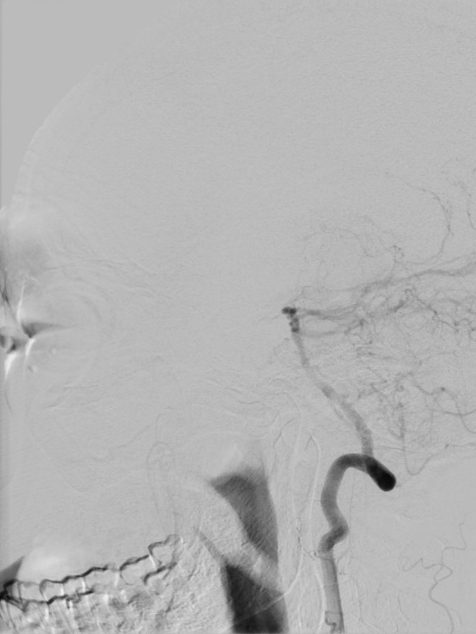

桡动脉入路行DSA:右侧颈内动脉C1段重度狭窄。